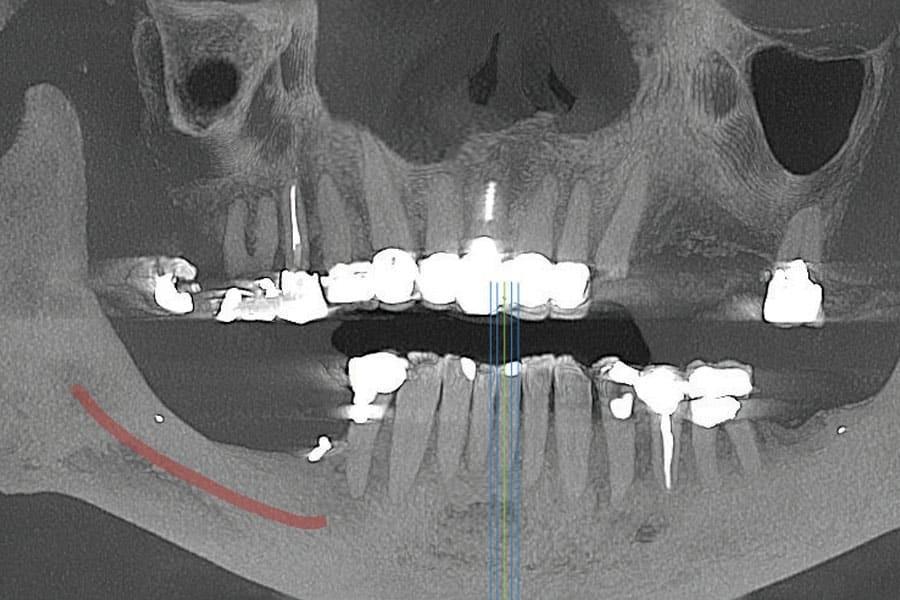

Панорамный рентгеновский снимок, полученный на основе КЛКТ, показал скошенный вертикальный дефицит костной ткани в правом боковом отделе нижней челюсти с недостаточной высотой кости для установки дентальных имплантатов выше нижнего альвеолярного нерва (Фото 1). КЛКТ левого верхнечелюстного квадранта выявила разрушенный левый клык с достаточным объемом кости для установки имплантатов в области клыка и второго премоляра.

Фото 1. Предоперационный панорамный рентгеновский снимок, полученный на основе КЛКТ, демонстрирующий вертикальную атрофию кости в правом боковом отделе нижней челюсти.